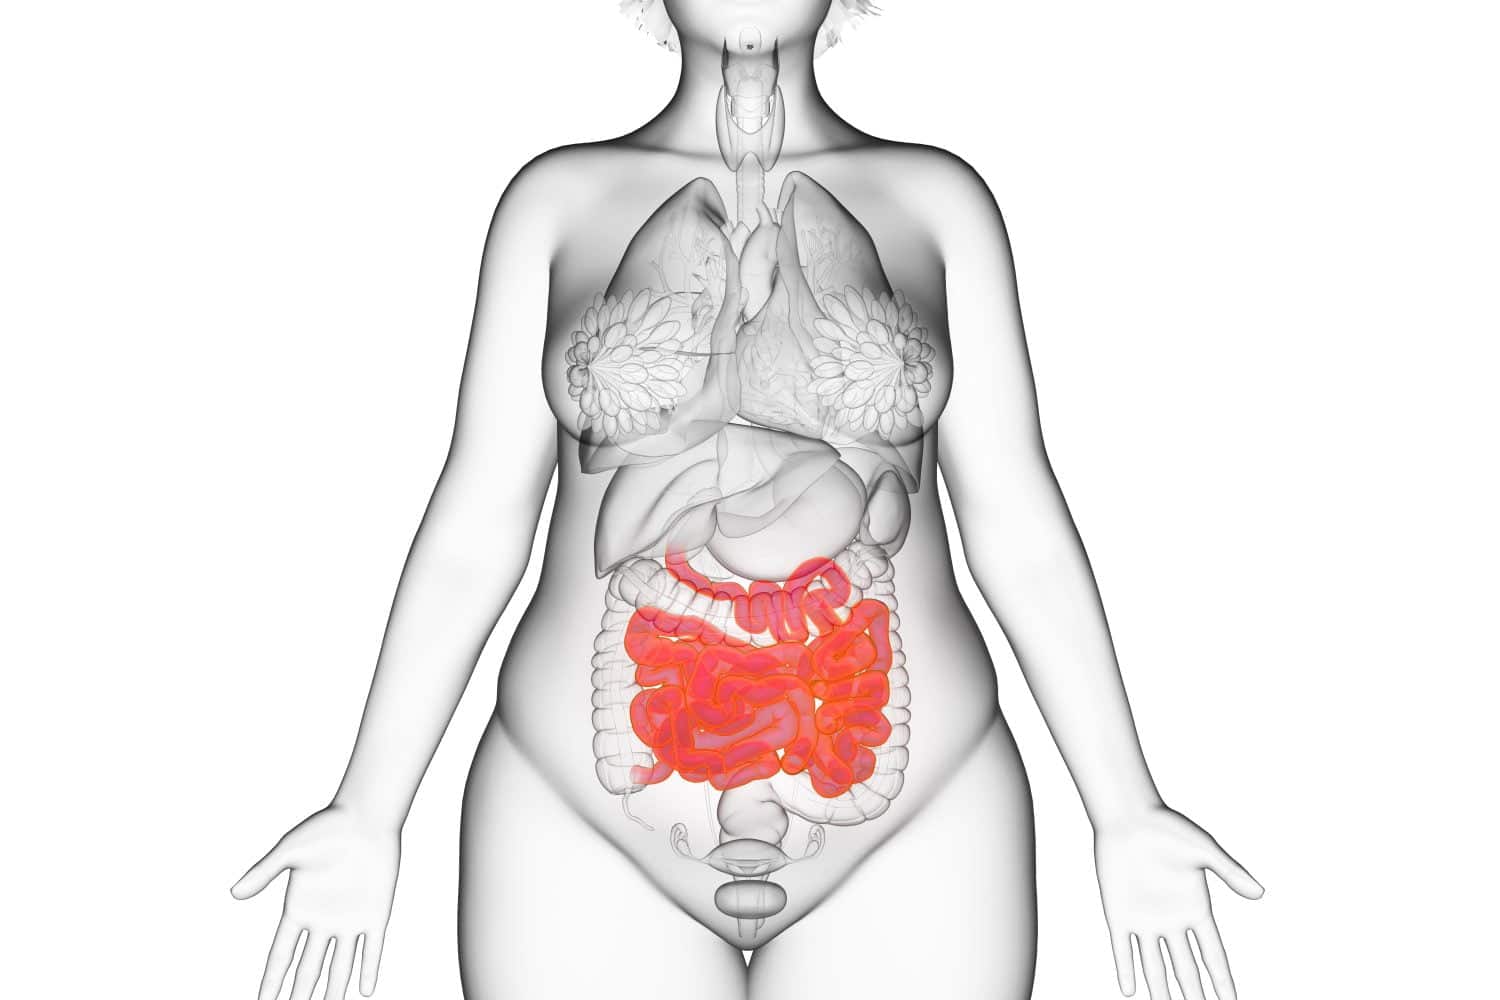

La microbiota intestinal o la flora intestinal vive con las células humanas del intestino. Además de las células que juegan un papel directo en la digestión, el intestino consiste en unos 500 millones de neuronas. Por eso al intestino se le llama a veces el «segundo cerebro». La microbiota contiene más de 300 especies diferentes de bacterias y juega un papel importante en el proceso de digestión.

Los investigadores encontraron 8 grupos de microbiota relacionados con la cantidad de grasa en el cuerpo. Cuatro comunidades microbianas parecían desarrollarse más en los niños y adolescentes obesos que en los que tenían un peso normal. Se encontraron cantidades más pequeñas de los otros 4 grupos microbianos en los participantes obesos en comparación con los delgados. La microbiota intestinal identificada en los jóvenes obesos tendía a ser más eficiente en la digestión de los azúcares que la de los niños y adolescentes de peso normal.

Estos hallazgos muestran que los niños y adolescentes obesos tienen una composición diferente de la flora intestinal que los niños y adolescentes delgados. Podrían desarrollarse modificaciones específicas de las especies que componen la flora intestinal humana para prevenir o tratar los primeros casos de obesidad en el futuro.

Además, los investigadores han descubierto que los niños con obesidad tienden a tener niveles más altos de pequeñas cadenas de ácidos grasos en la sangre que los de peso normal. Las pequeñas cadenas de ácidos grasos pueden convertirse en grasa en el hígado y acumularse en el tejido graso. Esta asociación podría indicar que los niños con un cierto tipo de bacterias intestinales podrían estar en riesgo a largo plazo de desarrollar obesidad.